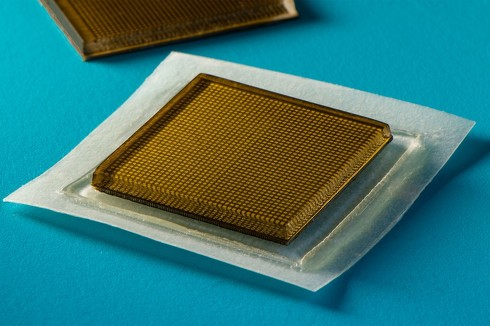

说到这里,就该本篇文章的主角出场了。本次介绍的工作,就是在这一趋势影响下的最新的研究进展,研究人员成功将体积庞大的超声成像探头,集成在一块小小的粘性贴片上——长宽2cm,厚度为3mm。

本文报告了一种生物粘附超声(BAUS)装置,该装置由一个薄且坚硬的超声探头组成,并通过一种柔软、坚韧、抗脱水材料制成的耦合剂层和生物粘附性水凝胶-弹性体混合物牢固地粘附在皮肤上(图1,B到D)。

BAUS探头有着高密度的元件(每平方厘米400个单元),这使得它在身体动态运动下具有稳定的元件位置,以及在长期应用中有着较高的可靠性。BAUS耦合剂能有效地传递声波,使BAUS探头免受皮肤变形的影响,并在48小时内保持牢固舒适的皮肤粘附力。

BAUS探头由中心频率为3、7或10MHz的高性能压电元件阵列组成(图1,E和F)。每个元件由BAUS探头的顶部和底部电路控制。这些电路可以通过三种技术制作:3D打印(图1F)、激光刻蚀和光刻,他们分别能达到100、10和1μm的电路线分辨率。同时,利用优化后的声学匹配层覆盖在底部线路上从而增强到皮肤的声波传递能力,将优化后的声学背衬层覆盖在顶部电路上来抑制共振效应。BAUS探头由一层环氧树脂密封,使其在长期应用中具有高稳定性和可靠性。本文还设计了一种即插即用的输入输出,并将其与柔性扁平电缆连接。BAUS探头的厚度为3mm,长度和宽度为1-2cm,重10-40g。